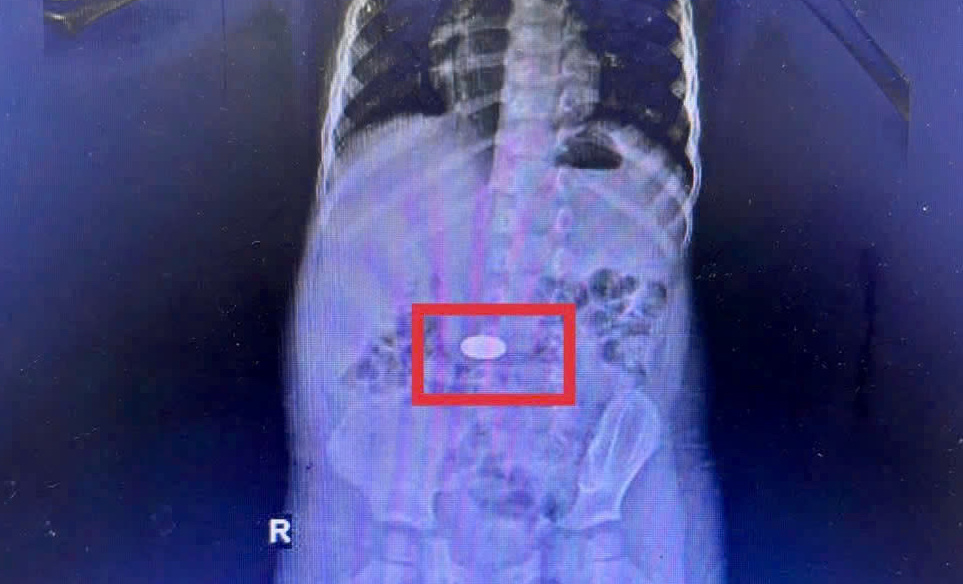

Gia đình cho biết bé vô tình nuốt đồng xu khi đang chơi. Kết quả chụp CT cho thấy dị vật nằm trong dạ dày. Các bác sĩ đã khẩn trương nội soi và lấy ra đồng xu vào rạng sáng 26-11. Bé đã ổn định và xuất viện sau đó.

Đồng xu nằm trong dạ dày trẻ. Ảnh: BV Đa khoa Khánh Hòa